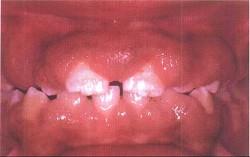

问题 药物性牙龈增生的临床表现是 ( )

选项 A.龈乳头可呈球状、结节状 B.上下前牙区较重,一般不易出血 C.只发生于有牙区 D.最根本的治疗是停药或换药 E.以上全是

答案 E